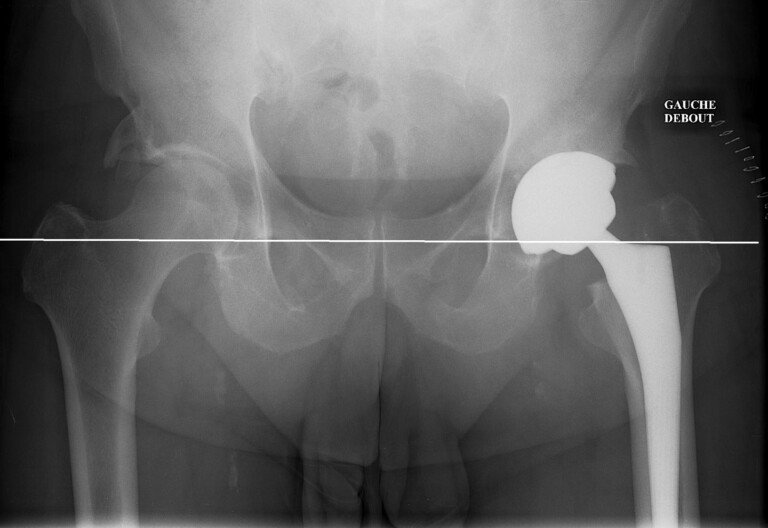

Clinicaccess vous propose des services de haute qualité en matière de chirurgie orthopédique maroc, notamment l’intervention chirurgicale qui vous permet la pose d’une prothèse de la hanche totale qui constitue le remplacement définitif des malheureux cartilages qui ont connu une…

La polyclinique Ibn Rochd à Marrakech a acquis au fil de ses 40 ans d’existence une expérience non négligeable au sein des différentes branches de la chirurgie moderne, parmi elle la traumatologie et l’orthopédie. La première est une spécialité chirurgicale…